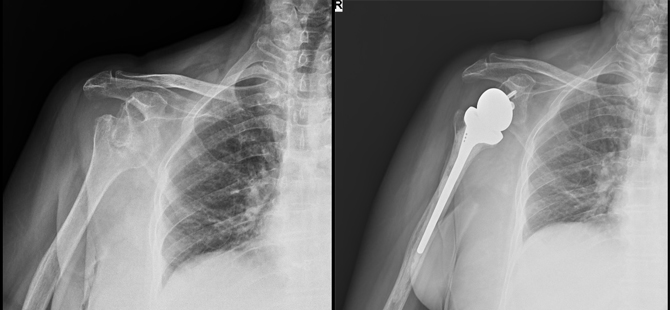

Once at MIOT, she was examined by the Shoulder and Upper Limb specialist. He advised for X-rays. She was diagnosed to fracture of the right shoulder. The doctor suggested for Reverse Shoulder Arthroplasty surgery of Right shoulder.

Mrs. Mahalakshmi was taken for surgery on 1st December 2017. Her post-operative period was uneventful. 3 days post surgery; she was advised to start physiotherapy. She had no pain in her shoulder region post surgery. 1 month later, she was able to lift her hands to a considerable extent. In 3 months time, she was able to move her right hand in all directions, even above her head. Now she can do all her activities and happily lift her granddaughter.